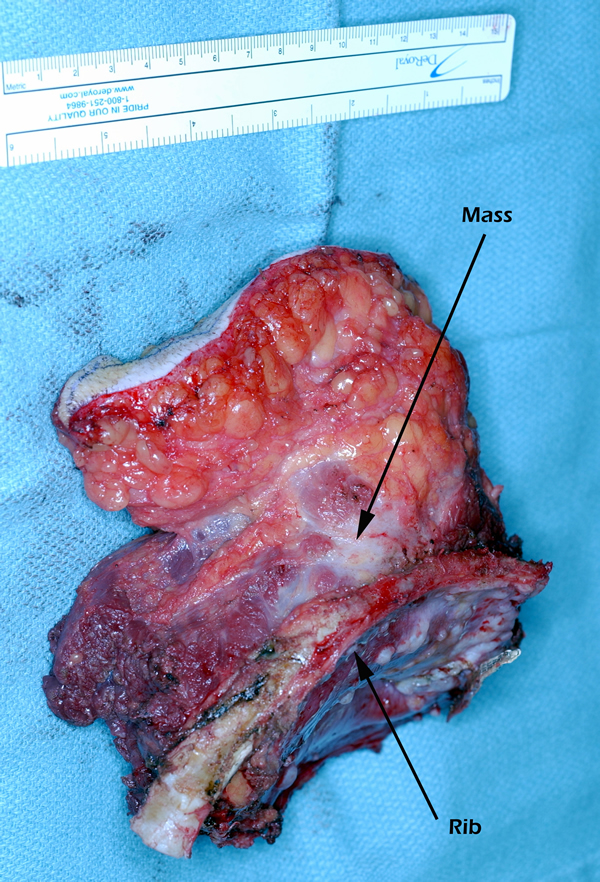

Eleven months later, he presented with a several month history of a painful fixed, firm mass over the pectoral area of the left chest and a smaller mass inferior to this (Figure 1). CT scan demonstrated a new 2 cm nodule in the left upper lobe associated with an anterior chest wall mass six centimeters in size in addition to bilateral new pulmonary nodules (Figure 2). The mass was tethered to the skin and in danger of eroding through it. The patient underwent en-bloc resection of the chest wall and adjacent lung (Figures 3a-c). The resulting defect (Figure 4a) was reconstructed with 2 mm Gore-Tex patch (Figure 4b) and pectoralis major muscle flap (Figure 4c) with primary skin closure (Figure 4d). The pathology revealed metastatic chordoma (Figures 5a-d). The patient recovered well, leaving the hospital on the sixth postoperative day.